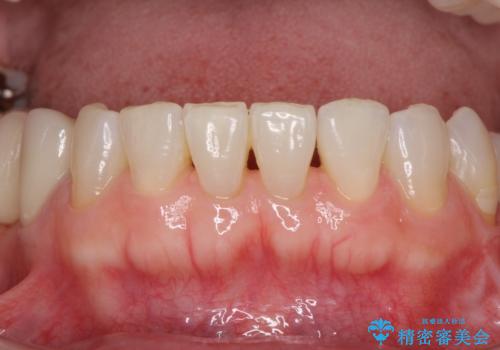

- 口の中に気になるところが沢山あるものの、地元ではなかなか治療を行ってくれるところがないとのことで、沖縄県の離島より来院された患者様です。

金属を使用した前歯のブリッジや奥歯の銀歯は全てオールセラミッククラウンまたはセラミックインレーとし、左下の奥歯はインプラントにより治療を行うこととしました。

外科処置を行うため、治癒を待つ期間が数ヶ月あるため、その期間を利用して下顎前歯のスペースを矯正治療で閉じることとしました。

矯正治療までは考えていなかったそうですが、物が挟まっていた前歯のスペースがなくなり、矯正治療を行って良かったとのことでした。